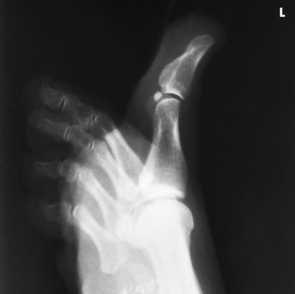

The ankle joint is commonly called the ankle mortise, or mortise joint. It is formed by the articulations between the lateral malleolus of the fibula and the inferior surface and medial malleolus of the tibia (Fig. 6-13, A). The mortise joint is often divided specifically into the talofibular and tibiofibular joints. These form a socket type of structure that articulates with the superior portion of the talus. The talus fits inside the mortise. The articulation is a synovial hinge type of joint. The primary action of the ankle joint is dorsiflexion (flexion) and plantar flexion (extension); however, in full plantar flexion, a small amount of rotation and abduction-adduction is permitted. The mortise joint also allows inversion and eversion of the foot. Other movements at the ankle largely depend on the gliding movements of the intertarsal joints, particularly the one between the talus and calcaneus.

Structures shown: The image shows a true AP projection of the ankle joint, the distal ends of the tibia and fibula, and the proximal portion of the talus.

NOTE: The inferior tibiofibular articulation and the talofibular articulation are not “open” or shown in profile in the true AP projection. This is a positive sign for the radiologist because it indicates that the patient has no ruptured ligaments or other type of separations. For this reason, it is important that the position of the ankle be anatomically “true” for the AP projection shown (Fig. 6-92).